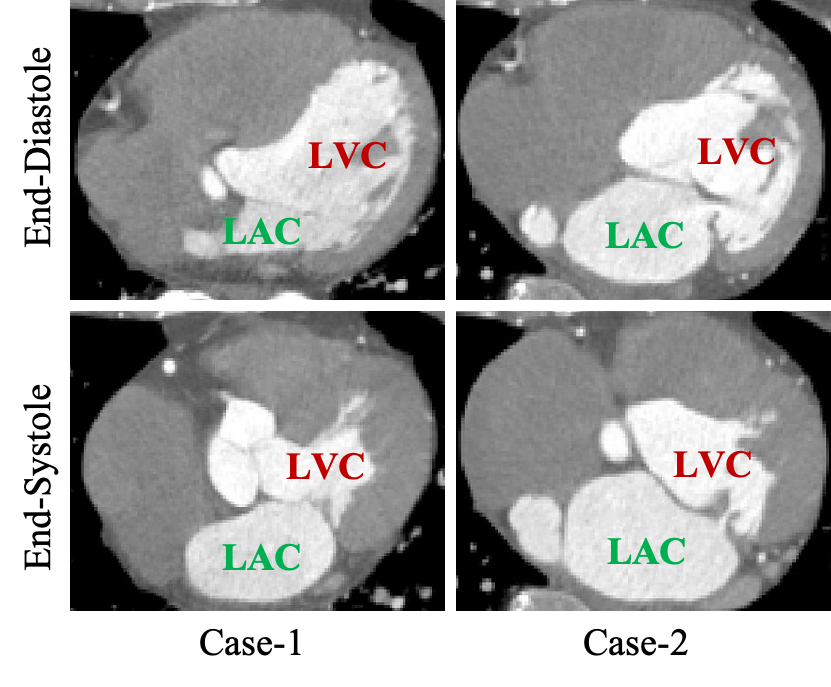

Refer to caption

Figure 1: Examples of 4D cardiac imaging of two patient cases, respectively of the two columns. The temporal variation between the image sequence can be large, i.e., between end-systole (ES) and end-diastole (ED) shown in two rows. All images are shown in trans-axial views and cropped to focus on the heart. LVC indicates the left ventricle cavity, while LAC indicates the left atrium cavity.

Technically, motion estimation is to establish corresponding deformation field between two time-point images which can be attained by image registration methods [6, 7]. Image registration is a broad topic and widely applied in various fields, e.g., image reconstruction [8, 9], image super-resolution [10], and atlas-based segmentation [11, 12], etc. Particularly, in our prior work [13], we presented a supervised interpolation network leveraging image registration to improve the sequential sampling rate for individual subjects. Conventional image registration approaches derive the motion field between two input images (usually referred to as the fixed image and moving image) by solving an optimization problem, which aims to maximize the image appearance similarity under certain smoothness regularization [14, 15]. However, these methods are typically time-consuming (or computationally expansive) via the iterative optimization process. Besides, when coping with large deformation, such as in cardiac motion between the two ends of the motion cycle (end-systole (ES) and end-diastole (ED), as shown in Fig. 1), non-physiological misestimation may happen as the price of excessive pursuing of appearance similarity.